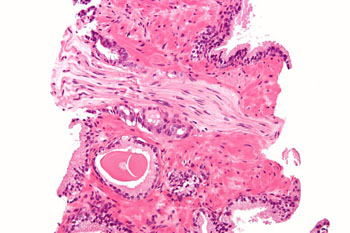

图片:前列腺腺癌产生神经周入侵的显微图像,传统型(腺泡型)是最常见的前列腺癌。前列腺活检,H&E染色(图片来自Nephron和Wikimedia)。